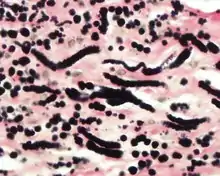

Histochemistry

The elastic fibers will be highlighted by a Weigert or von Gieson elastic stains.[9]